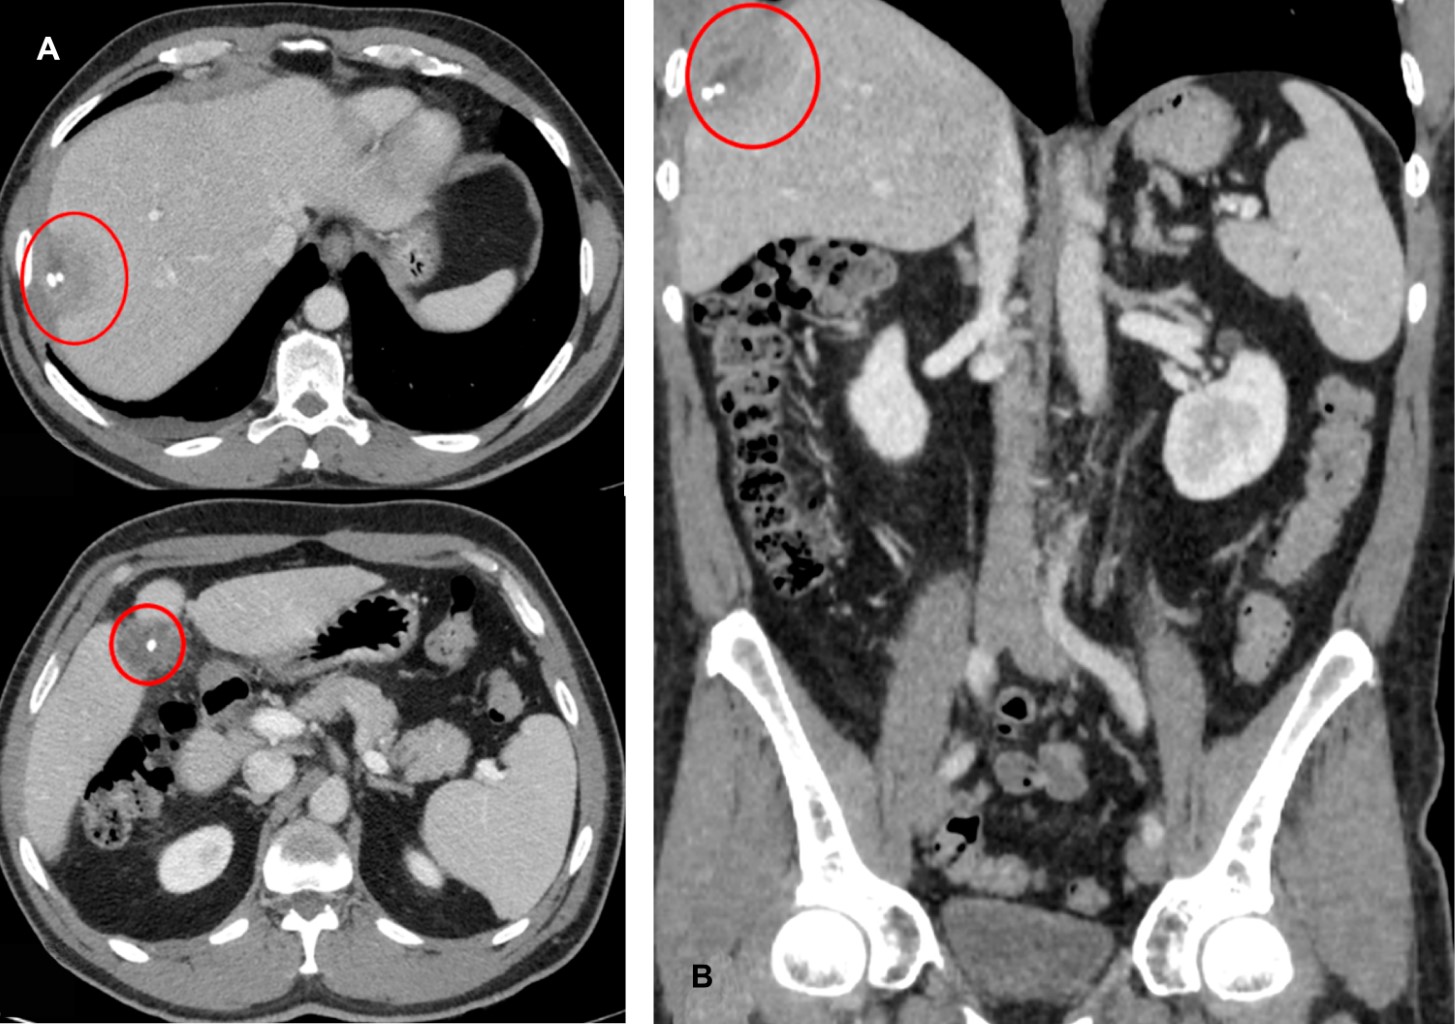

Se decide realizar pruebas complementarias de imagen, comenzando por una ecografía abdominal que evidencia una lesión heterogénea bien delimitada con calcificaciones en su interior ubicada en el lóbulo hepático derecho, lo cual plantea como primera opción diagnóstica la existencia de un absceso hepático (Figura 1). Ante la existencia de la lesión y la persistencia de la clínica, se decide ampliar el estudio mediante una TAC de urgencia para una mejor filiación de la misma. Se realiza una TAC abdominal con contraste intravenoso que pone de manifiesto la existencia de un discreto derrame pleural derecho, así como de una lesión de morfología ovalada con imágenes de densidad cálcica en su interior localizada en el espacio subfrénico derecho, y afectación hepática en el segmento VIII compatible con absceso o colección inflamatoria en dicho nivel. En el lecho quirúrgico de la colecistectomía se visualiza una imagen de predominio líquido, mal definida, que también presenta en su interior la presencia de litiasis (Figura 2).

Los hallazgos radiológicos y los antecedentes quirúrgicos del caso son compatibles con el síndrome de postcolecistectomía por litiasis residuales y afectación inflamatoria secundaria.

Los hallazgos radiológicos son fundamentales a la hora del diagnóstico definitivo. La ecografía abdominal manifiesta imágenes nodulares o lineales hiperecogénicas con sombra acústica posterior correspondientes con litiasis. La TAC mostrará lesiones heterogéneas de predominio hipodenso, con calcificaciones en su interior y realce periférico tras la administración de contraste intravenoso, con la presencia de líquido libre en espacio de Morrison o en el espacio subhepático en relación con las colecciones generadas alrededor de los cálculos abandonados.